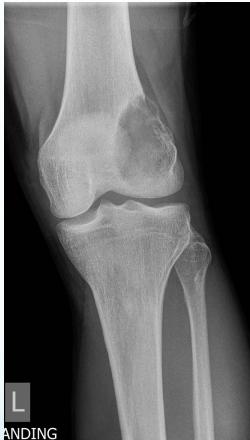

- X-ray:

- Osteolytic, moth-eaten

Source: https://radiopaedia.org